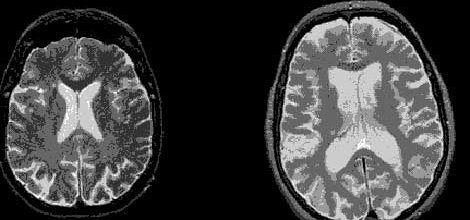

Genetik kökenli nörolojik bir hastalık olan Huntington hastalığı hareket bozukluğu ve zihinsel gerilik gibi belirtilerle kendini belli ediyor.

En belirgin belirtileri kol, bacak, gövde ve yüz kaslarında meydana gelen ani gerilmeler, muhakeme gücünün bozulması ve bellekle ilişkili problemler olarak sıralanan Huntington hastalığı, 10-20 yıllık bir dönemde gelişiyor ve belirtilerin ilk ortaya çıkmasının ardından, giderek artan bir hızla meydana gelen hücre ölümü ve sinirsel tahribata bağlı olarak, 10-15 yılda büyük oranda ölümle sonuçlanıyor.